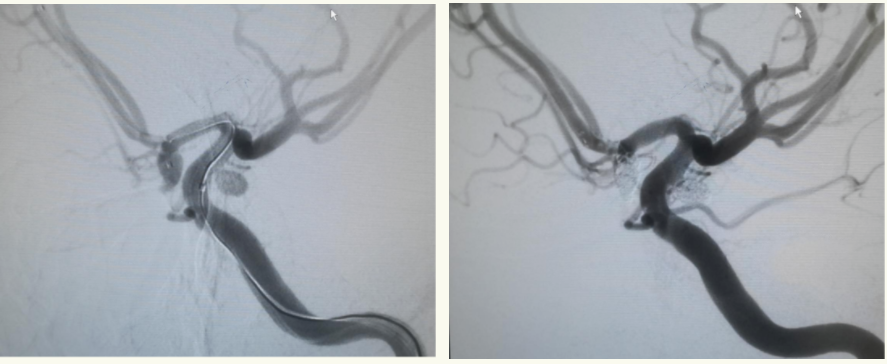

术中工作角度造影:证实动脉瘤栓塞满意,载瘤动脉通畅,颅内血管均通畅,血供良好。

手术前后造影对比,前后交通动脉瘤均消失,治疗效果满意。